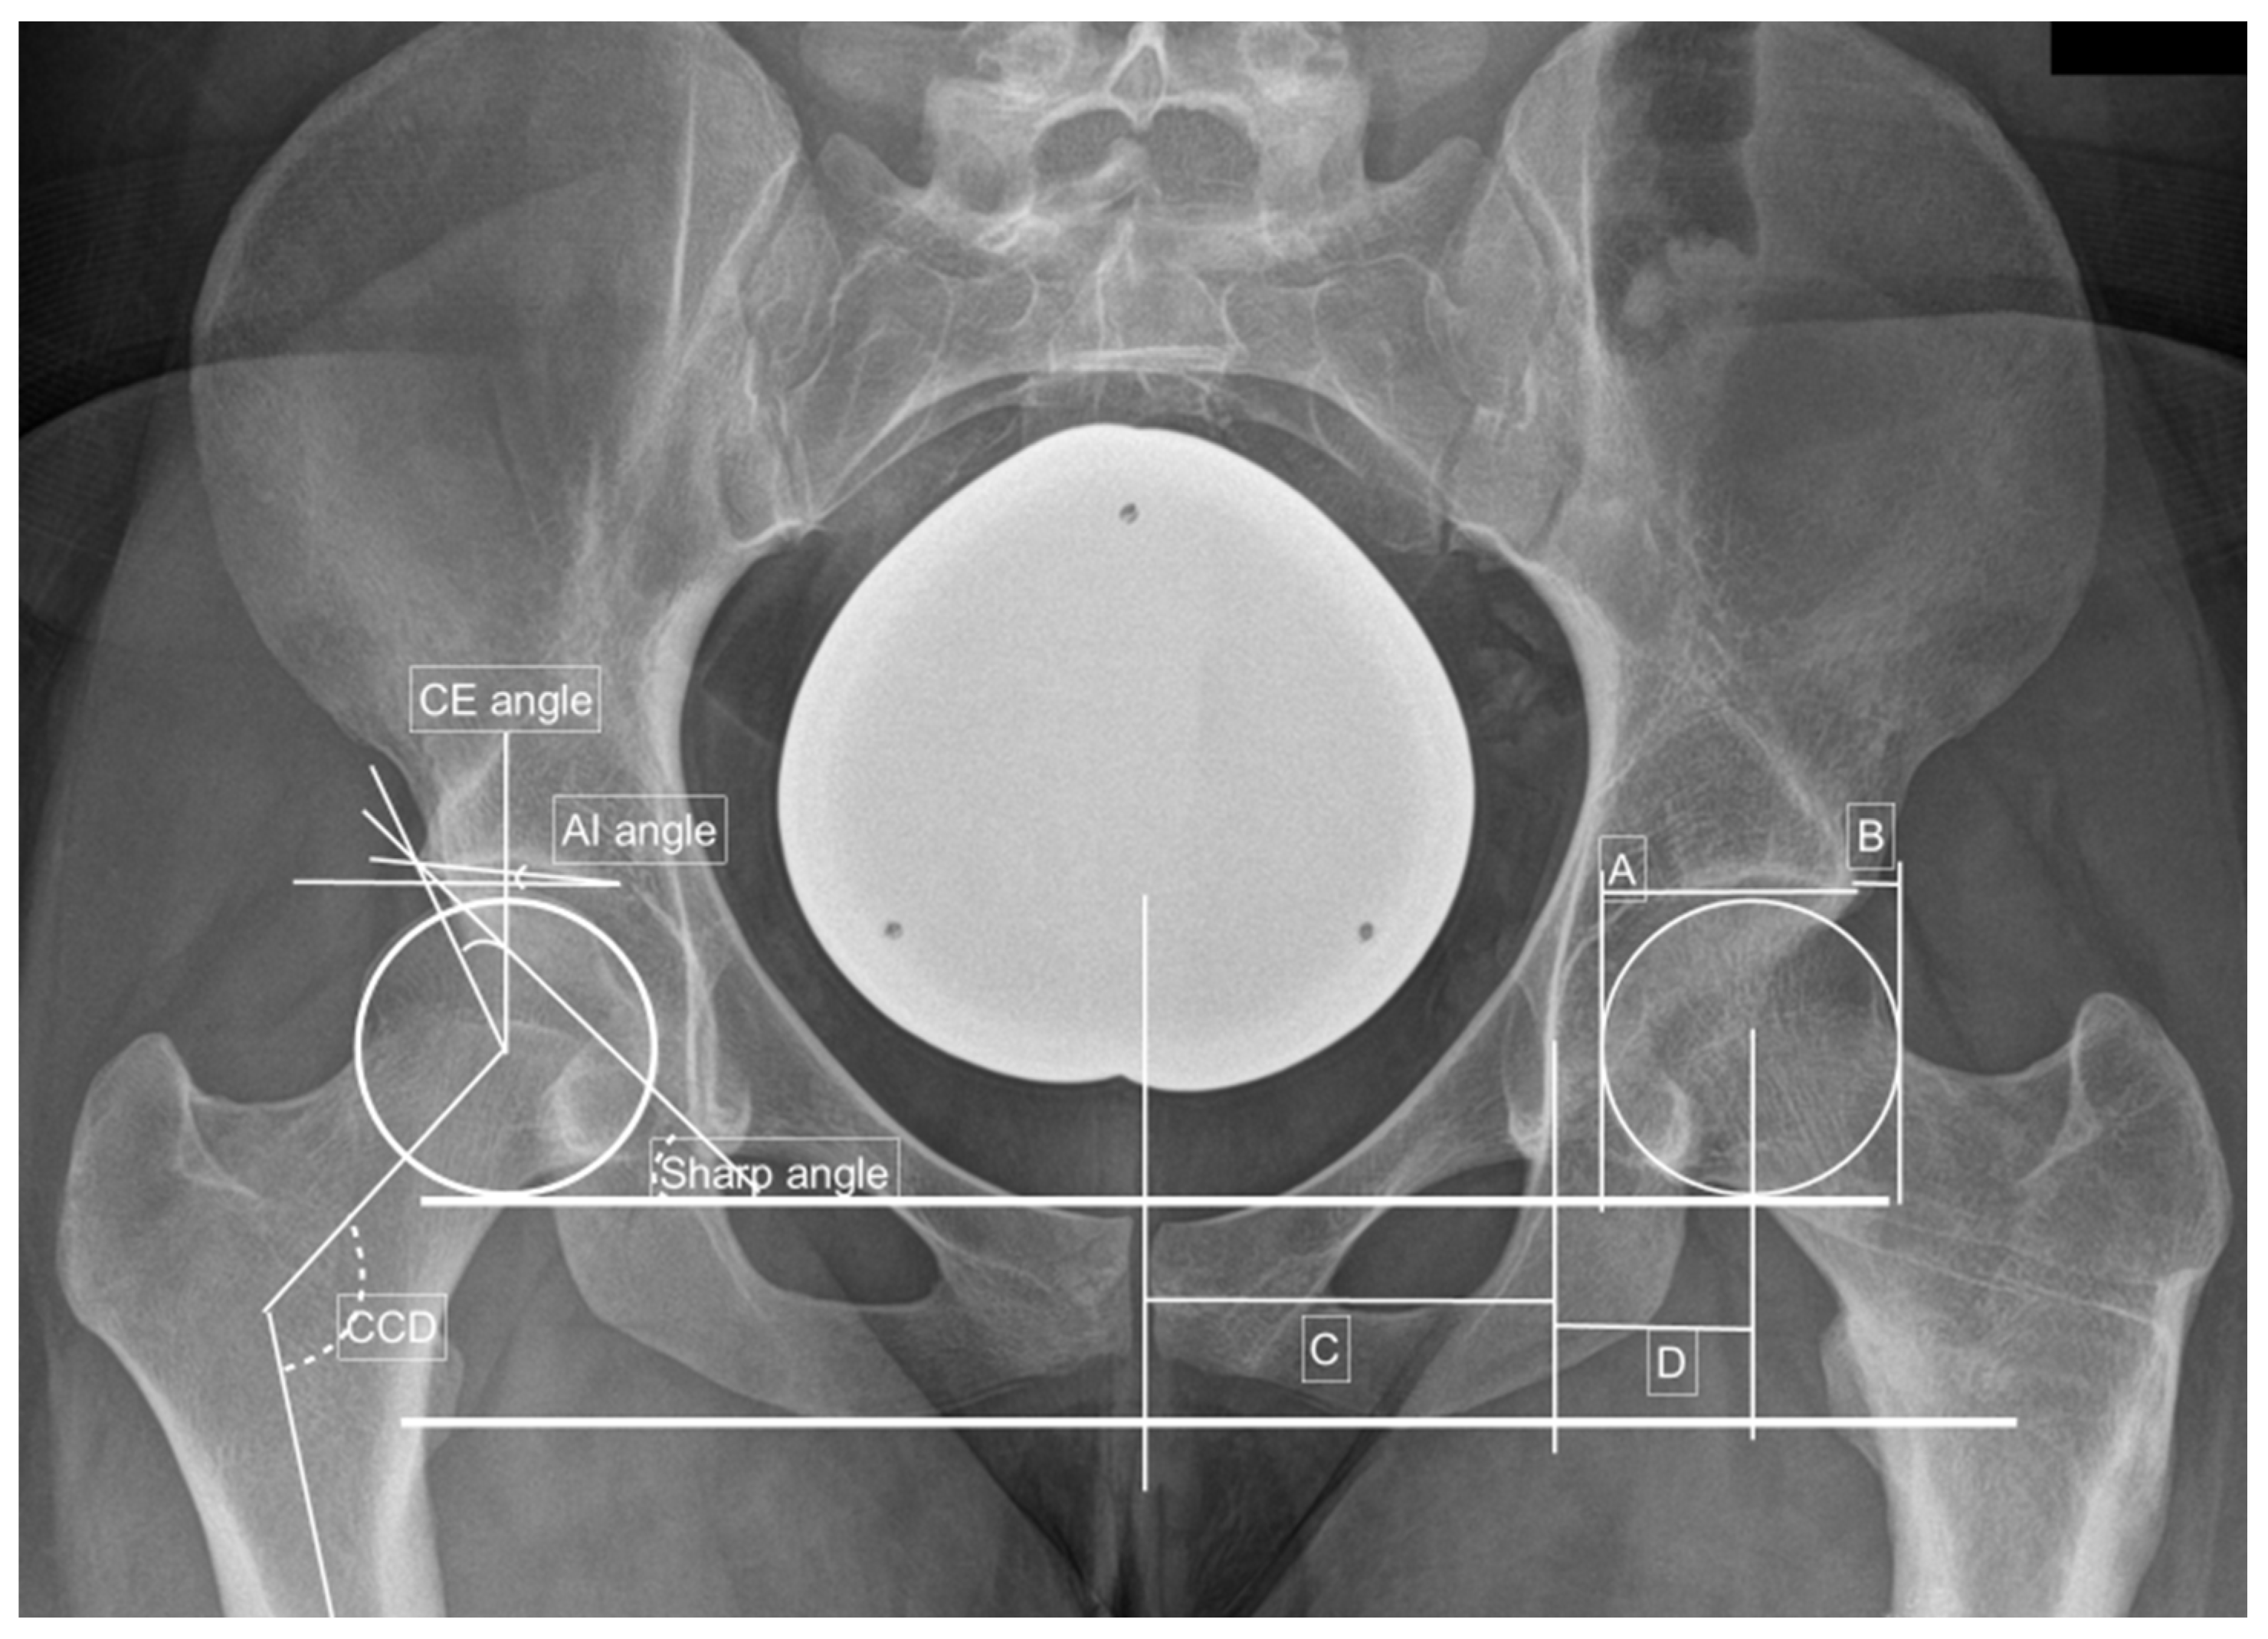

| CE angle (°) | 22.7 ± 5.8 | 0.002 | 0.968 | 21.0 ± 5.4 | 23.7 ± 5.8 | 0.050 |

| AI angle (°) | 11.2 ± 5.2 | 0.006 | 0.781 | 12.6 ± 6.3 | 10.3 ± 4.3 | 0.065 |

| Sharp angle (°) | 42.5 ± 3.7 | −0.005 | 0.894 | 43.3 ± 3.5 | 42.1 ± 3.8 | 0.148 |

| Hip lateralization index | 0.56 ± 0.06 | 0.617 | 0.590 | 0.57 ± 0.06 | 0.56 ± 0.06 | 0.214 |

| AHI | 23.2 ± 7.0 | 0.017 | 0.524 | 25.6 ± 5.7 | 21.9 ± 7.3 | 0.031 |

| CCD (°) | 133.0 ± 5.7 | <0.005 | 0.994 | 133.3 ± 6.4 | 132.8 ± 5.4 | 0.378 |

| Crossing over sign | 17 (32.7) | −0.194 | 0.184 | 4 (21.1) | 13 (39.4) | 0.091 |

| Kellgren–Lawrence score | 0.4 ± 0.5 | 0.015 | 0.909 | 0.4 ± 0.5 | 0.4 ± 0.5 | 0.488 |

| Alpha angle (°) | 100.0 ± 10.9 | −0.001 | 0.922 | 101.5 ± 10.0 | 98.8 ± 11.6 | 0.235 |

| Beta angle (°) | 57.0 ± 7.5 | 0.015 | 0.288 | 58.8 ± 7.8 | 55.7 ± 7.2 | 0.111 |